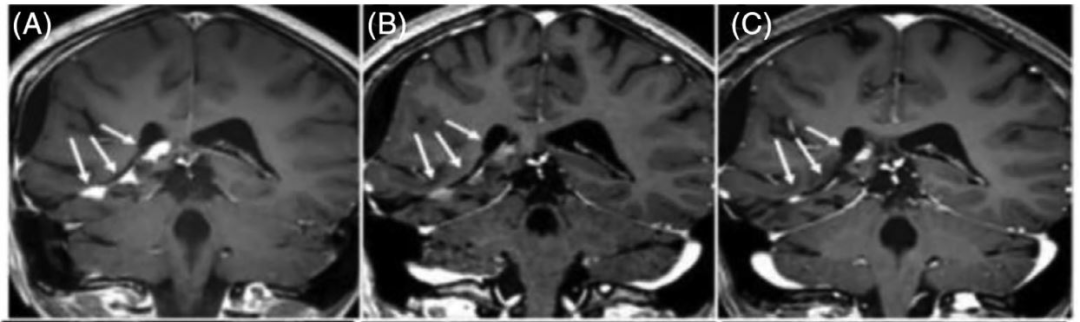

图2: 1例PR患者的病灶改变情况,分别为基线时、治疗18个月和4年时的MRI表现